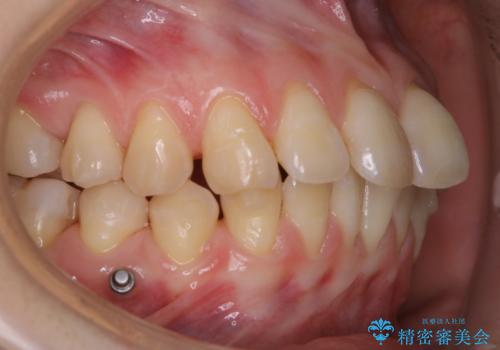

インビザラインでの治療中の患者様のクリーニング前後写真です。

- インビザライン矯正中に茶色が気になるとのことで来院されました。PMTC30分コースを行いました。